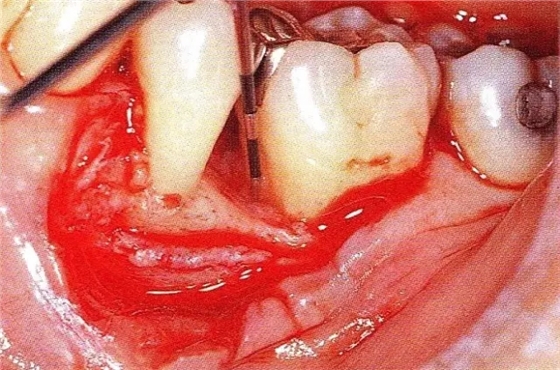

▲圖7-3將posterior interproximal類型的非吸收性覆膜修整后進(jìn)行垂直懸吊縫合做固定。垂直懸吊縫合后,確定覆膜是否會(huì)動(dòng)搖,再將齦瓣與之緊密縫合。

▲圖7-4術(shù)后1年2個(gè)月再翻開看的情況。與圖7-1的骨缺損狀態(tài)相比可知形成了臨床性骨再生。